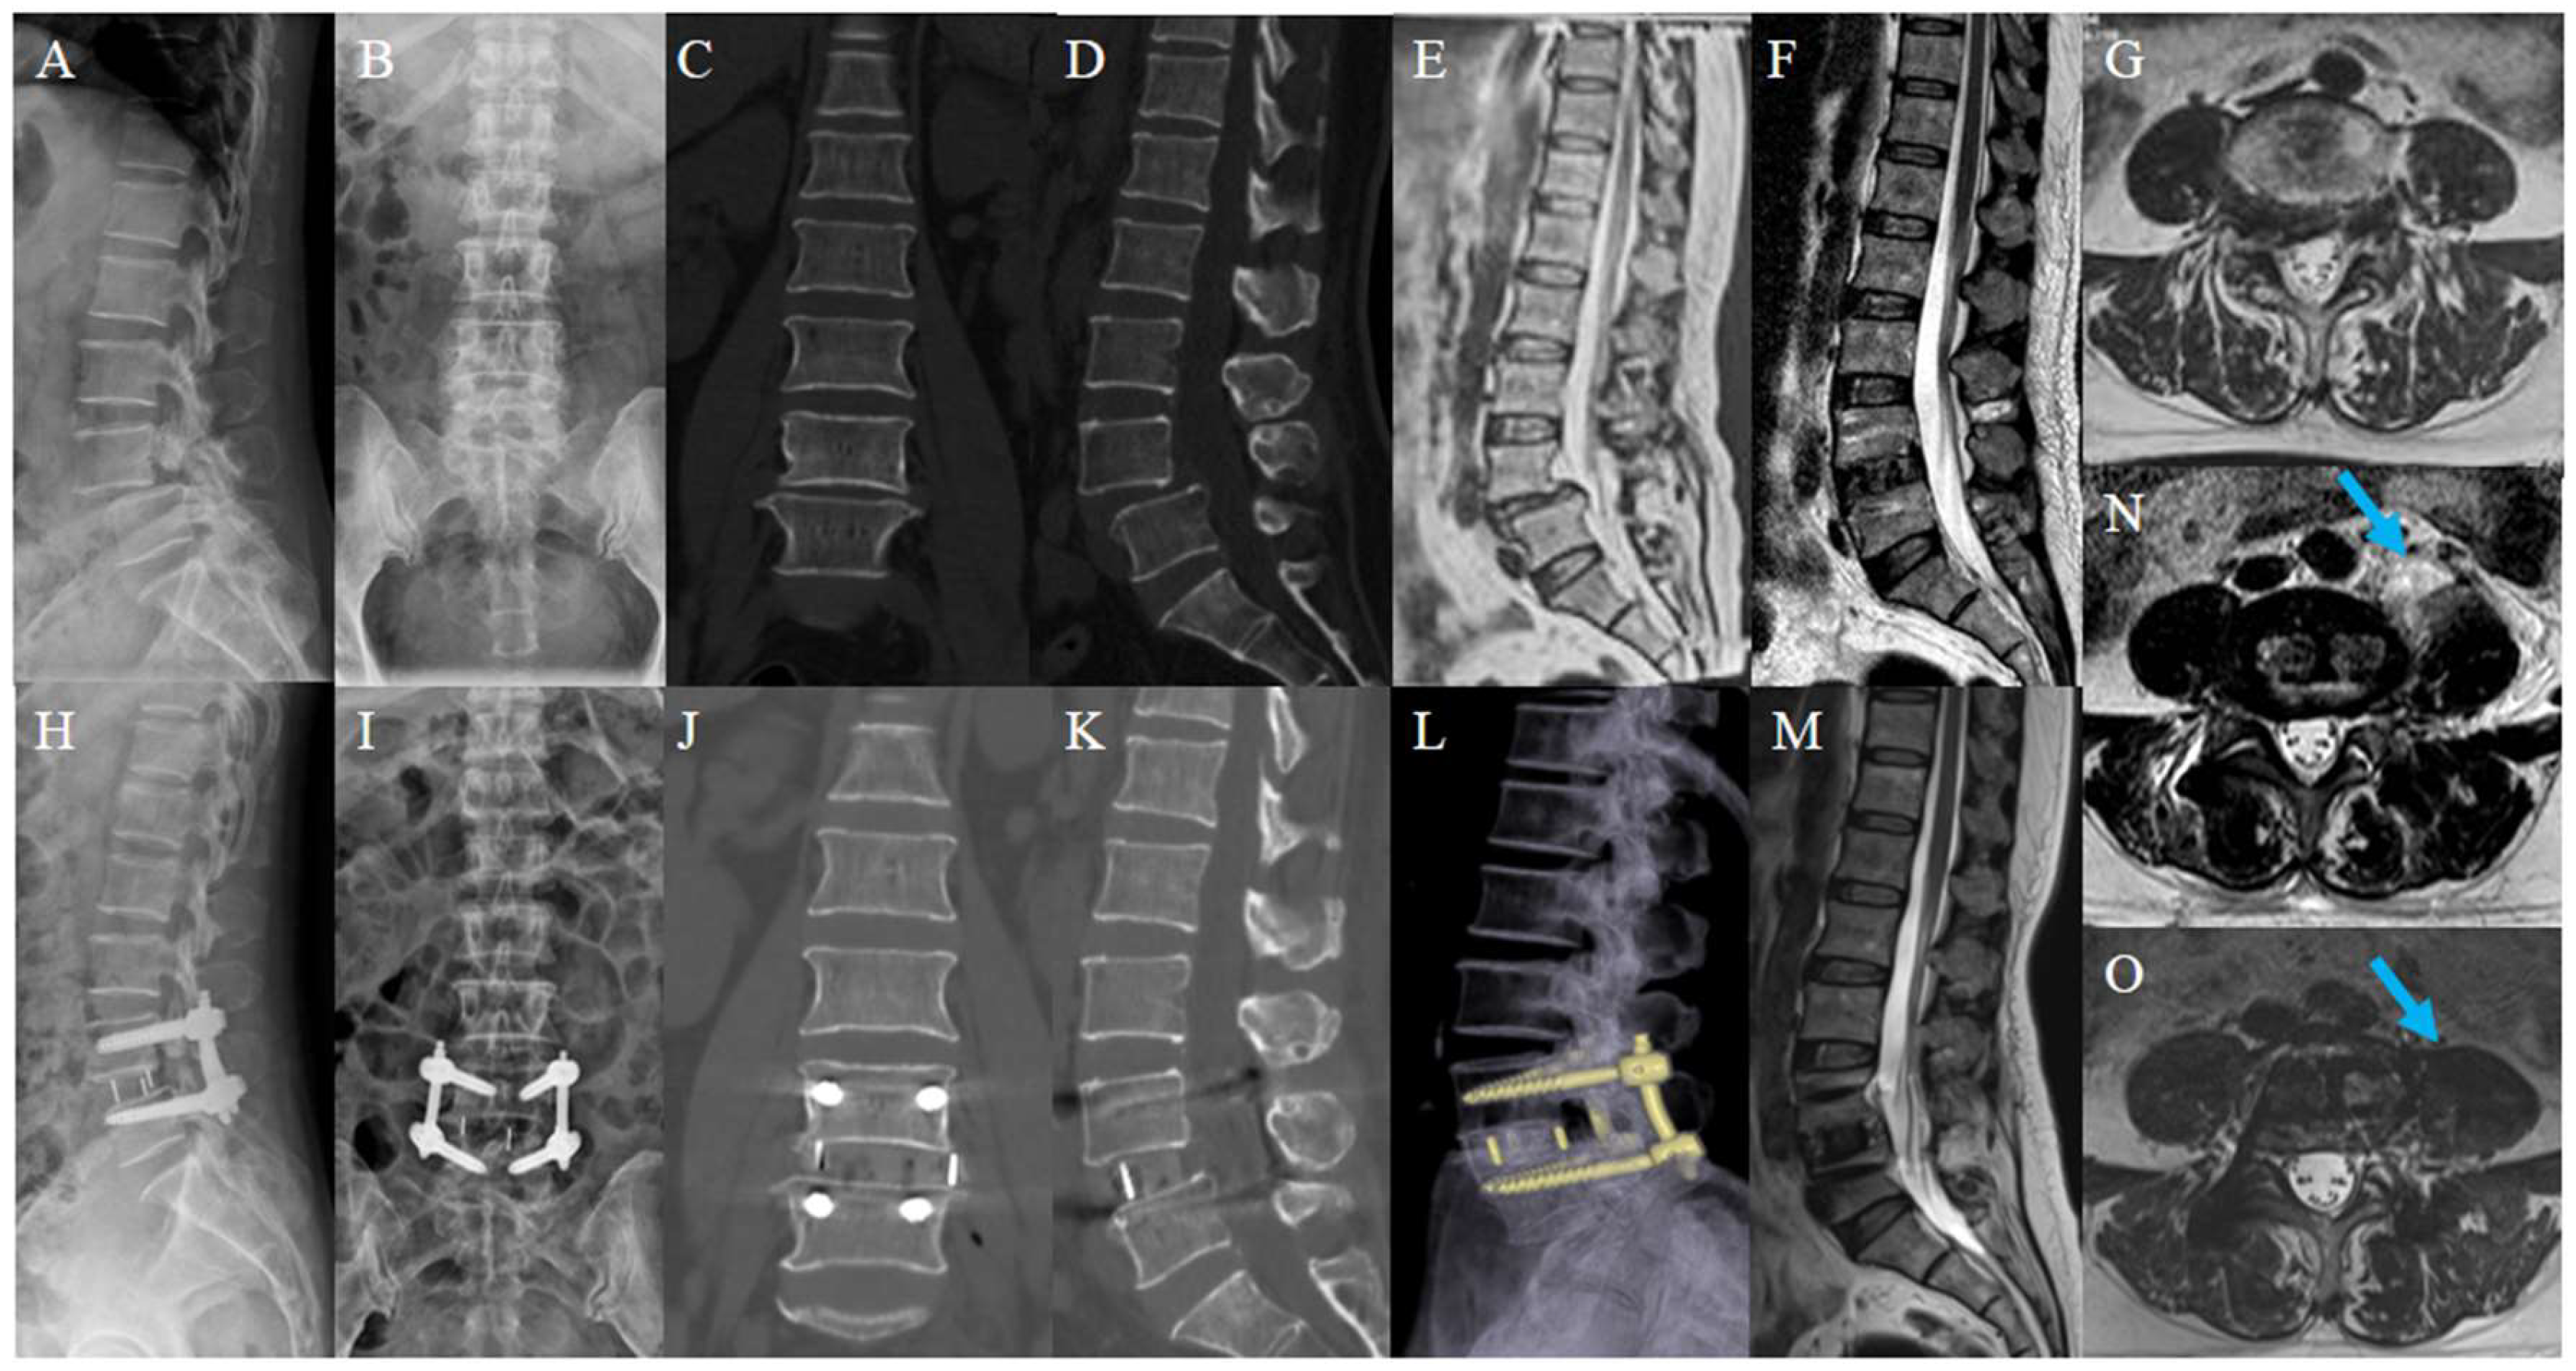

Figure 4.

Typical case. A 55-year-old woman, presented with pain and numbness in the right lower extremity for 5 years; her condition worsened for 3 weeks. Preoperative lumbar X-ray (A,B); preoperative lumbar CT (C,D); preoperative lumbar MRI. Preoperative images showed the L4 spondylolisthesis and stenosis at L4-5 (E,G); postoperative lumbar X-ray showed L4 was reduced (H,I); postoperative lumbar CT showed the distraction of disc height (J,K); postoperative lumbar MRI showed satisfactory decompression and a huge swelling of the left psoas major (arrow) (F,N). Lumbar CT reconstruction and MRI at 1-year follow-up showed solid fusion with no cage subsidence (L). Swelling of the left psoas major reduced significantly and its area recovered (arrow) (M,O).